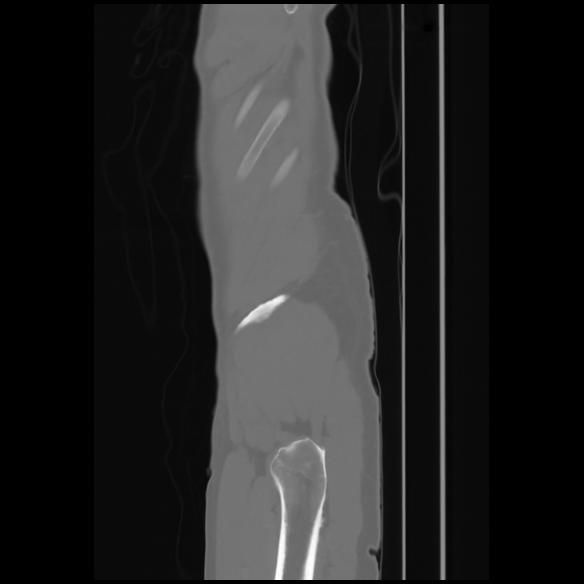

7 CUERPO,CE,Sagittal,3.000,CUERPO,Sagittal,